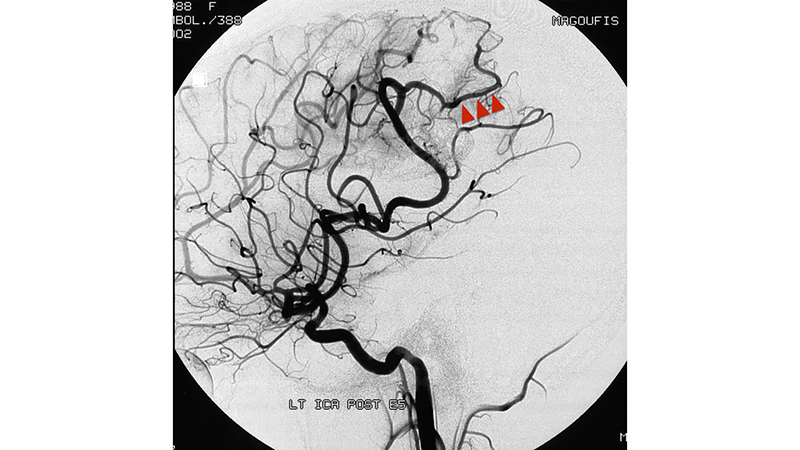

- Πλάγια λήψη εγχύσεως στην αριστερή έσω καρωτίδα. Διακρίνονται οι τρείς κύριοι τροφοφόροι κλάδοι που αρδεύουν της αρτηριοφλεβώδη φωλεά (μαύρα βέλη). Η φλεβική παροχέτευση γίνεται μέσω διατεταμένων βρεγματικών φλεβών προς τον άνω οβελιαίο κόλπο. Βλέπουμε τις εστιακές στενώσεις στο φλεβικό σκέλος που ευθύνονται γιά την αύξηση της πιέσεως μέσα στην φωλεά και γιά την αιμορραγία (κόκκινα βέλη).

- Πλήρης εξάλειψη της δυσπλασίας. Βλέπουμε την αδιάλειπτη συνέχεια του βρεγματικού κλάδου που φαίνεται μετά την απόφραξη της επικοινωνίας(αιχμές κόκκινων βελών).